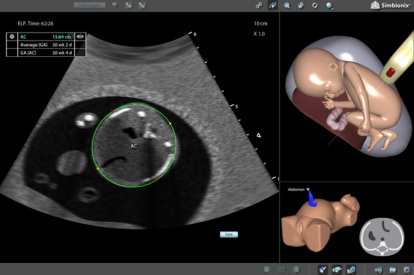

Ultrasound Mentor accelerates the development of basic to advanced technical and cognitive skills, by providing not only the probe manipulation training, but also a didactic environment enabling structured, self-guided learning including step-by-step instructions and educational aids such as 3D anatomical map and probe positioning assistant, all backed up with our progress monitoring tool MentorLearn.

- Advanced diagnostic tools, including Color Doppler, CW, PW, M-mode, and measurements

OB 2nd Trimester Module

“The simulator has allowed our residents, fellows and sonographer students to systematically review fetal anatomy. The fetal movement during the exam replicates real life scanning in a way that dramatically…

Terry C Harper, MD

University of Colorado Anschutz Medical Campus